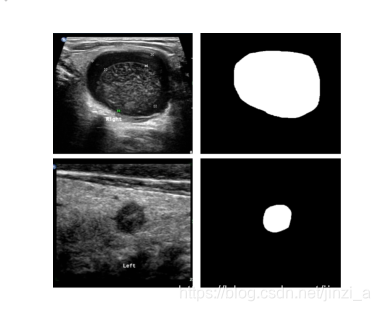

下图为 甲状腺结节超声图像示例以及对应的二进制边界掩膜。这个地方存在疑问,这个二进制边界是怎么弄出来的,数据集自带的吗?